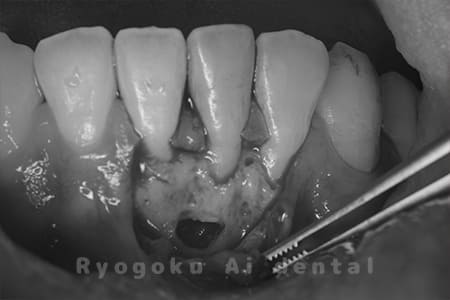

下の前歯の違和感が取れない、響く感じも強いとのことでご来院された患者様です。歯根端切除術を行い、術後の経過も良好です。

<リスク・副作用>

外科手術のため、術後に出血、痛みや腫れ、違和感を伴います。口腔内の状態によっては適応できないことがあります。歯根端切除で治らなければ抜歯を検討しなくていけない場合もあります。